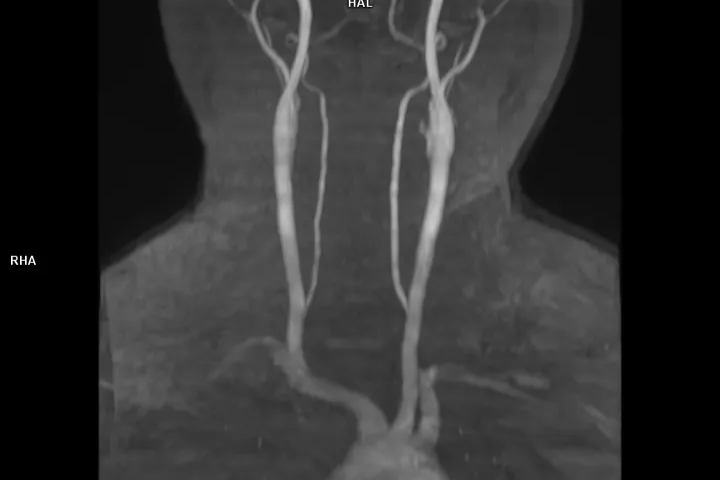

控糖不力,并发症悄然而至——影像学评估心、脑、肾、足风险